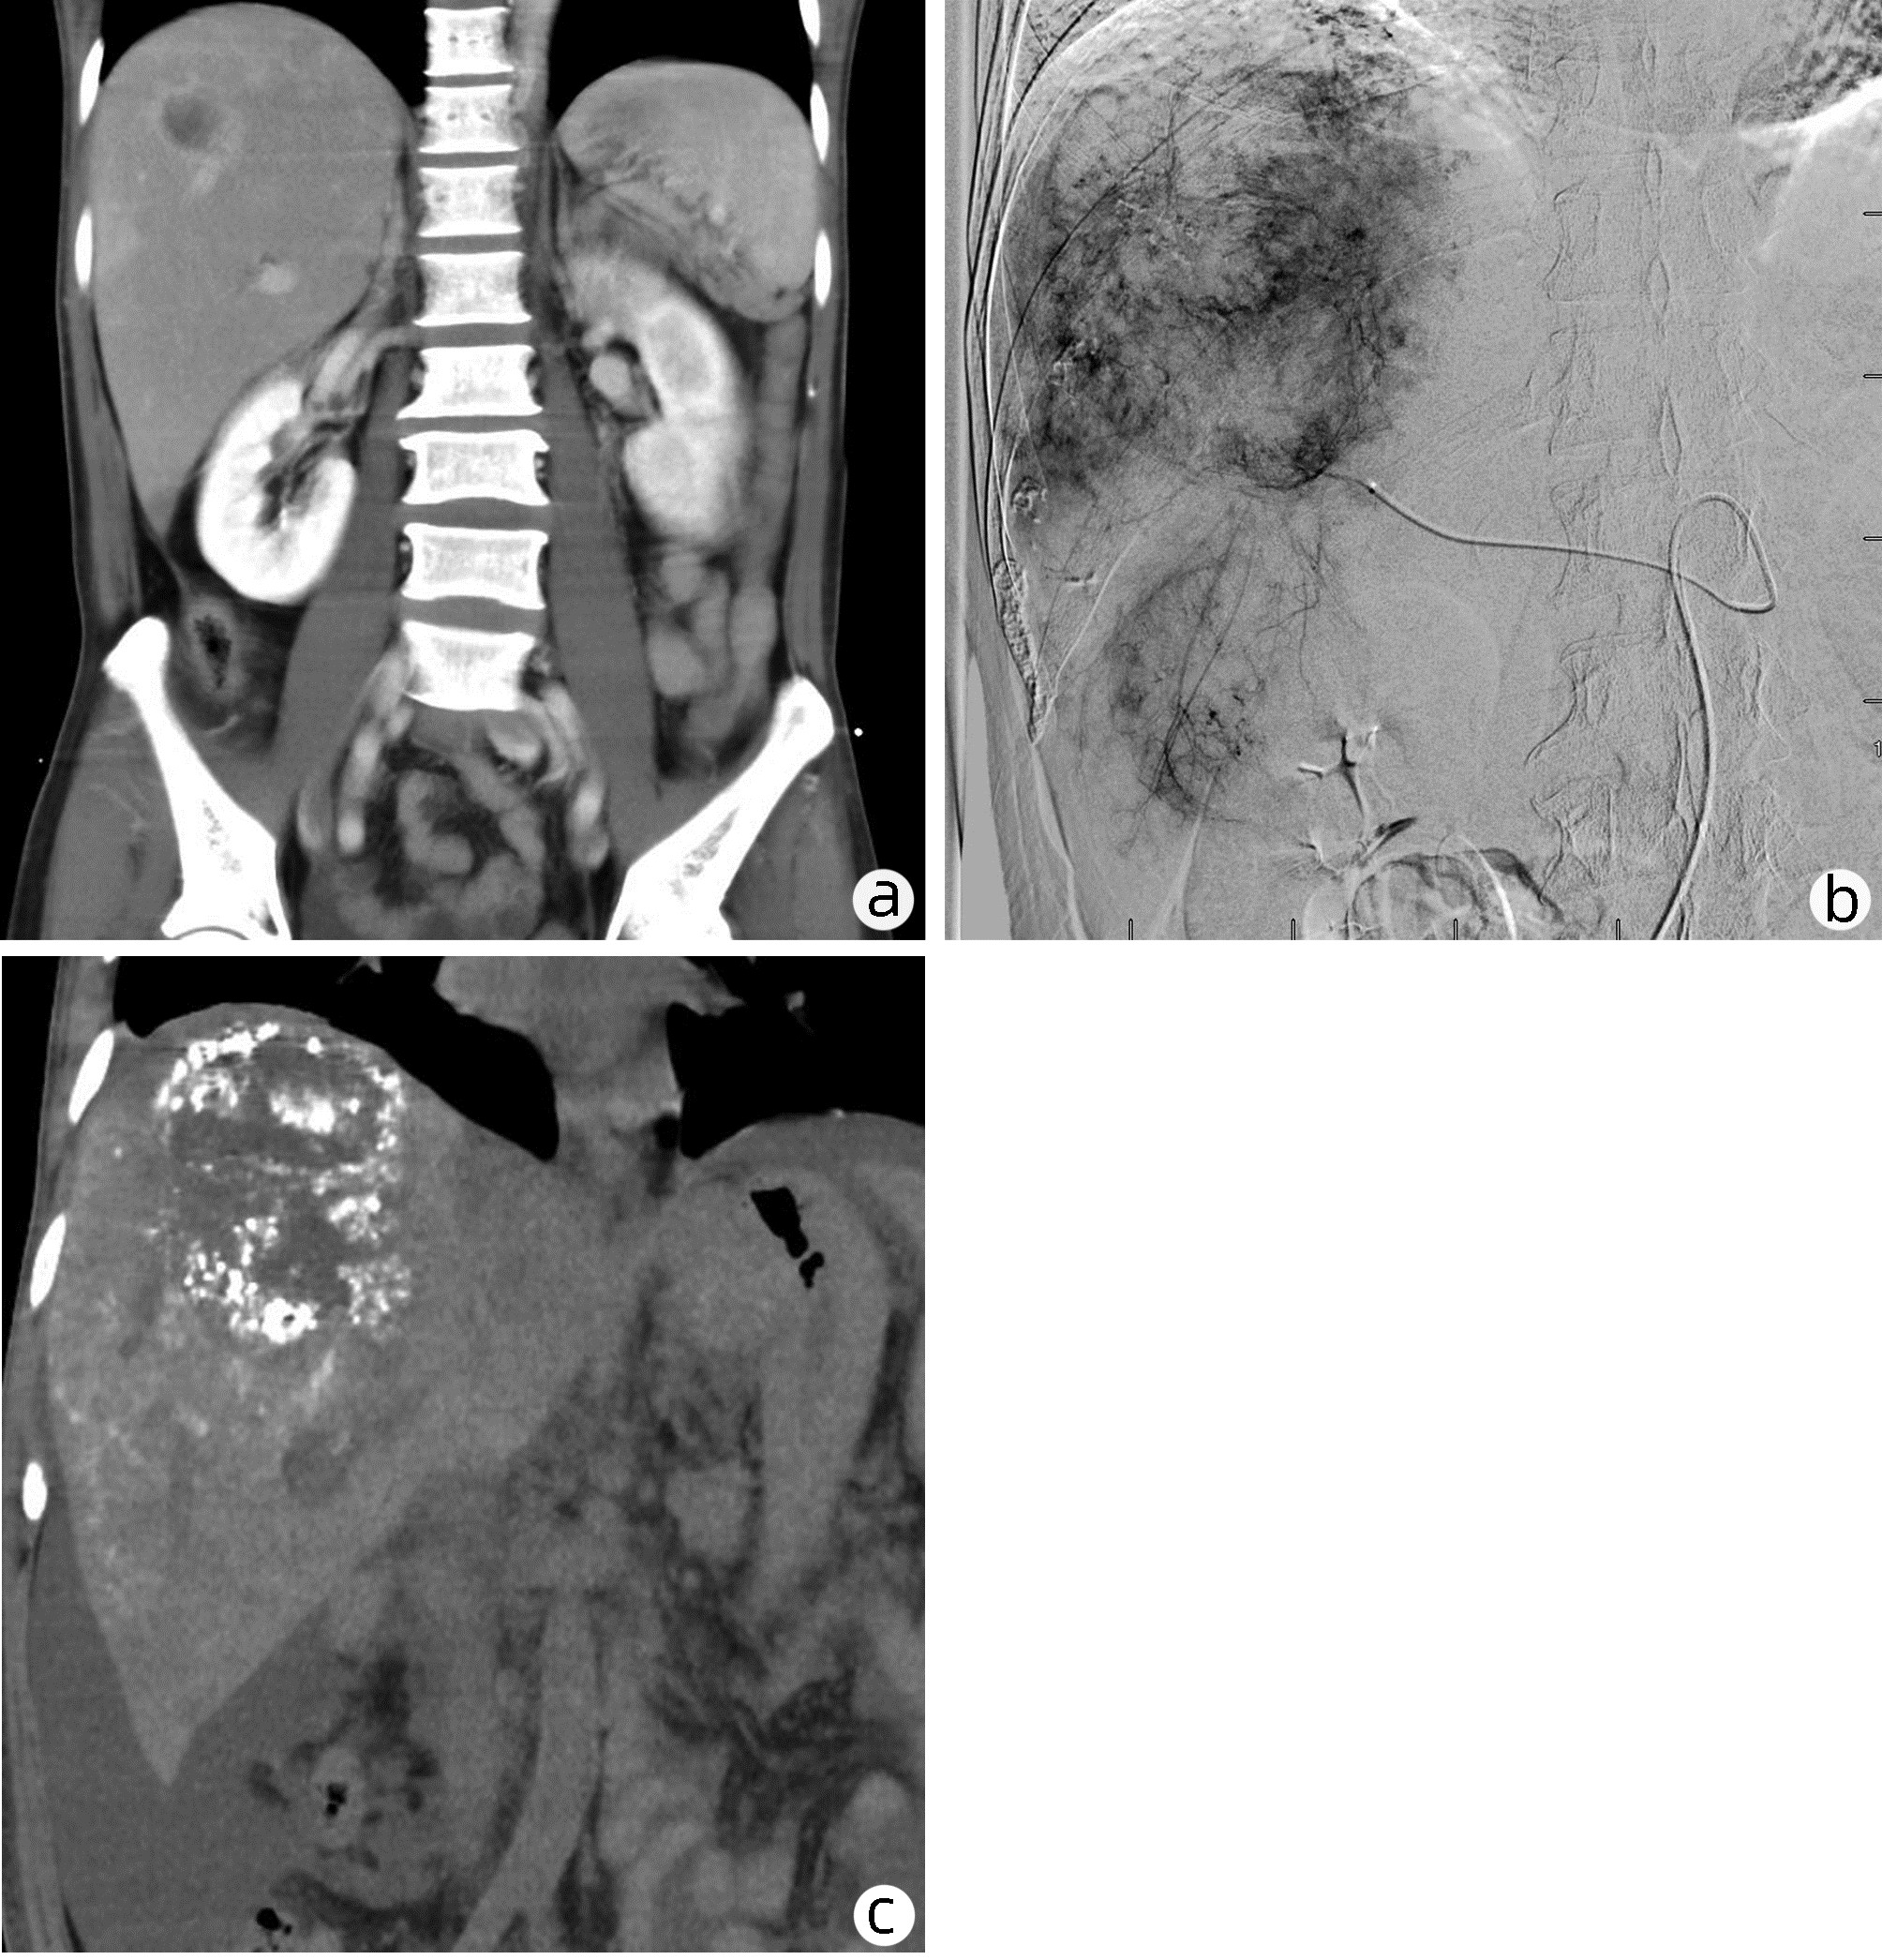

Prognostic value of KRAS mutations in patients with advanced primary liver cancer treated with transcatheter arterial chemoembolization

Xuchu LIU, Shiyun QIN, Lijun CHEN, Juan CHEN, Xiaoguang YOU

2022, 38(11): 2514-2519. DOI: 10.3969/j.issn.1001-5256.2022.11.015

Abstract(1162) HTML (252) PDF (2594KB)(53)

Abstract:

Objective  To assess the prognostic value of KRAS mutation in patients with advanced primary liver cancer treated with transcatheter arterial chemoembolization (TACE).  Methods  Ninety-seven patients with advanced primary liver cancer who received TACE treatment in The Third People's hospital from April 2017 to May 2020 were included. The mutation status of KRAS was detected, and its relationship with the prognosis of TACE was investigated. The t-test was used for comparison of continuous data between two groups, and the chi-square test was used for comparison of categorical data between two groups. Survival analysis was performed using Kaplan-Meier survival curve and compared using Log-rank test. Cox regression analysis was performed to identify the prognostic factors.  Results  Among 97 patients with advanced liver cancer, KRAS mutations were detected in 34 patients (35.05%), including 21 patients with codon 12 mutation (61.76%) and 13 patients with codon 13 mutation (38.24%). KRAS mutation was associated with liver cirrhosis, intrahepatic metastasis and the number of tumors (χ2=0.035, 3.965, and 6.593, all P < 0.05). Survival analysis showed that the progression free survival and overall survival were significantly longer in KRAS wild-type patients than in KRAS mutant patients (χ2=4.465 and 4.280, all P < 0.05). Multivariate Cox analysis revealed that KRAS mutation, intrahepatic metastasis, number of tumors and BCLC stage were important factors affecting the overall survival and prognosis of patients (all P < 0.05).  Conclusion  KRAS mutation is common in patients with advanced primary liver cancer and is closely associated with a poor prognosis after TACE. It may become a potential indicator of clinical prognosis.